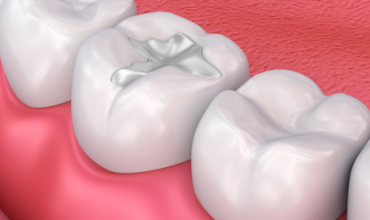

At Pranjal Dental Clinic, we offer a wide range of advanced dental treatments in Greater Noida to ensure complete oral health and beautiful smiles. Our services include root canal treatment, dental implants, smile designing, teeth whitening, cosmetic dentistry, tooth extraction, and painless dental care. With modern technology and expert care by Dr. Pranjal Sirohi, we provide safe, effective, and comfortable dental solutions for patients of all ages.